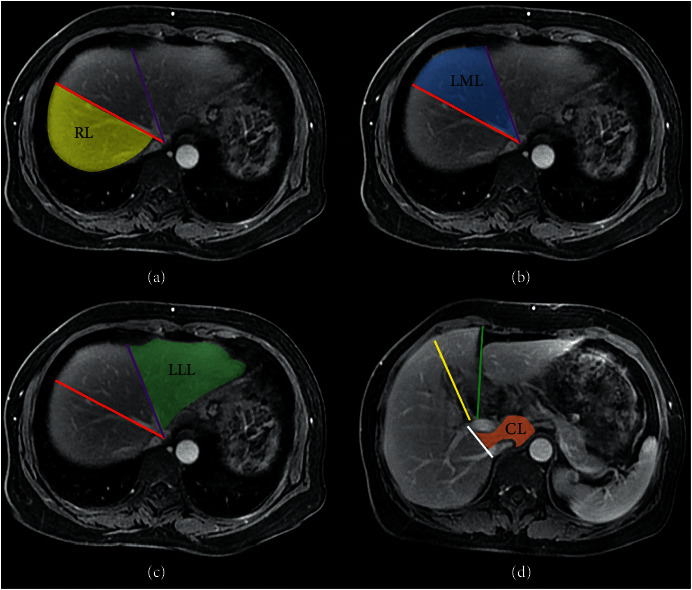

Methods: Forty-four consecutive patients with hepatitis B-related cirrhosis who underwent Gd-EOB-DTPA-enhanced MRI were divided into compensated and decompensated statuses based on clinical evaluation. Volume and signal intensity of individual lobes were retrospectively measured to calculate HUI of the right liver lobe (RHUI), medial (MHUI) and lateral (LHUI) left liver lobes, and caudate lobe (CHUI). Spearman's rank correlation analyses were performed to evaluate relationships of lobe-based HUI with Child-Pugh and model for end-stage liver disease (MELD) scoring system scores in compensated and decompensated statuses. The Mann-Whitney U-test was used to compare the lobe-based HUI between compensated and decompensated statuses. The performance of lobe-based HUI in distinguishing cirrhosis was evaluated using receiver operating characteristic (ROC) analysis, and the area under the ROC curve (AUC) was calculated as a measure of accuracy. Delong's method was used for statistical analysis to elucidate which HUI is optimal.

Abstract Image